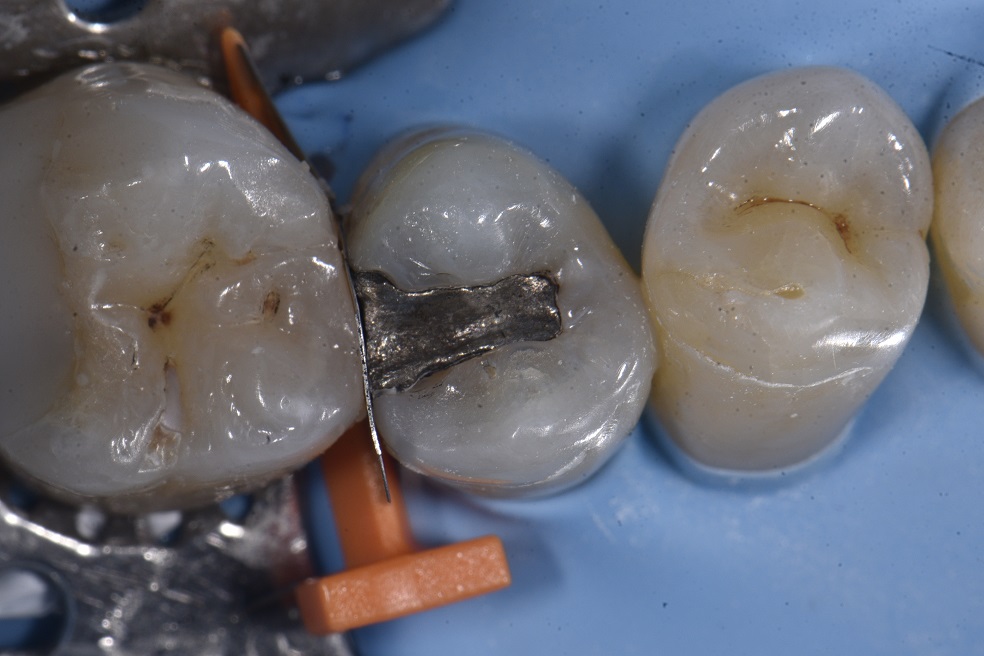

Had to cancel all my patients today as Morrow Street had a block-wide power surge yesterday that fried “something”. Not in the fuse department, nor the transformer down the road, possibly in the “pillar”, whatever that is. Anyways, sob story over. On generator power, I completed this 15DO amalgam replacement on my dad. Marginal defects had led to deep recurrent caries against the pulpoaxial wall which was completely invisible radiographically. Lesions are only visible radiographically when the lesion girth exceeds 1/3rd the buccolingual width of the respective tooth. The marginal ridge was accurately and anatomically recreated using the new #Garrison #Compositight_3D_Fusion system which features proximal wall wedge protectors so your neighboring tooth doesn’t look too “loved up” by your high speed bur.

The proximal fit and grip by this system on the premolar is almost “magnetic” and the most stable fit of any sectional matrix system I have tested to date. The results speak for themselves with a contact strength that makes you shiver with glee.

The restoration was layered to completion using a single shade of A3 Grandio Classic with fissure tinting courtesy of #Voco #FinalTouch tints.